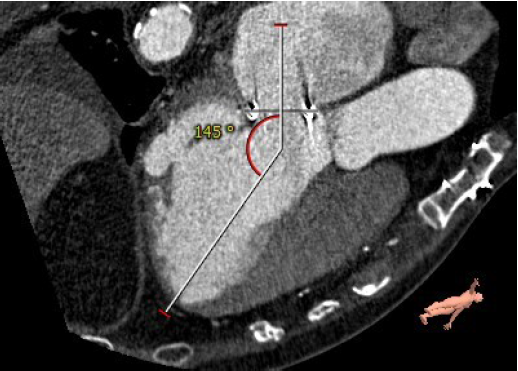

左室与生物瓣轴夹角145°